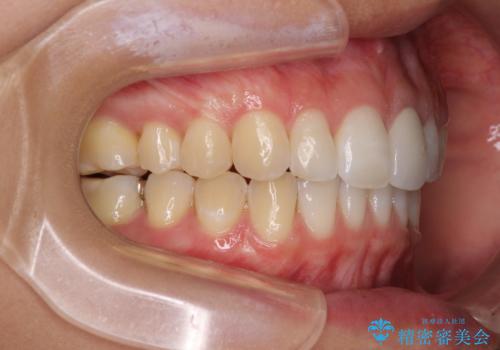

- 変色した前歯と突出した口元を気にして来院された患者様です。

口元の突出感はインビザラインにより歯列を整え、その後に、前歯をオーダーメイドタイプのオールセラミッククラウンにて補綴治療することとしました。

長時間のマウスピース装着と、患者様自身でのゴムかけに協力いただき、口元の突出感をしっかりと改善することができました。

前歯のオールセラミッククラウンもまるで本物の歯のように仕上がり、患者様には大変満足していただきました。